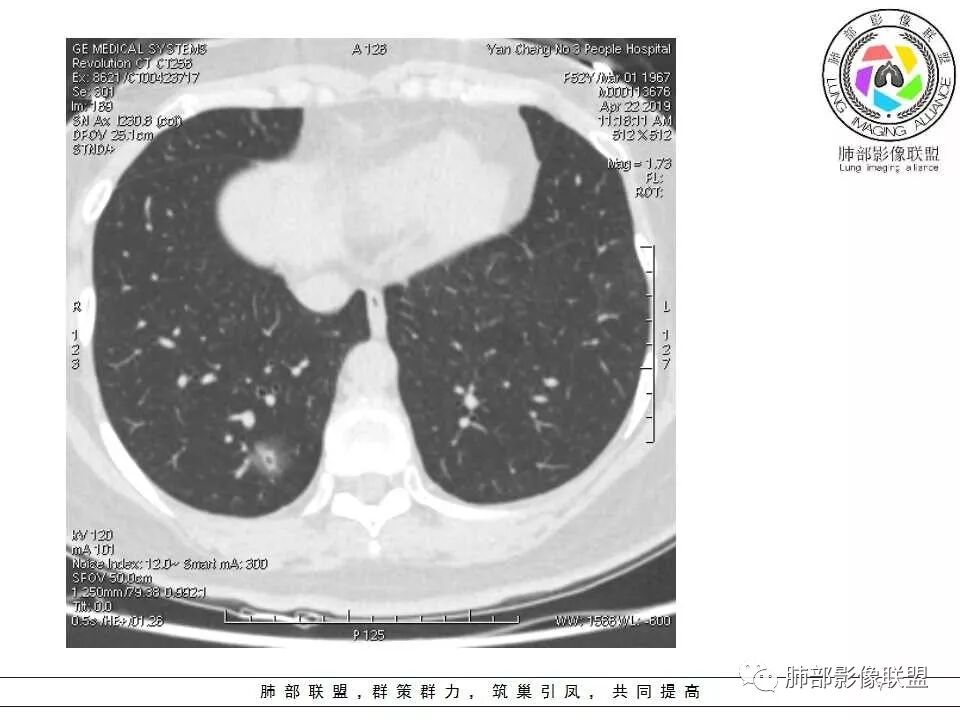

晨读:52f,体检发现右下肺结节,空洞、周围晕征(磨玻璃),局部血管影增粗,考虑1.真菌感染;2.GPA或不典型单发转移待排。

晨读:体检发现肺部结节,胸部CT:右下肺混合密度结节,结节中心空泡,壁光滑,结节边缘模糊,软毛刺,结节血管相对清楚,考虑良性结节可能,抗炎后复查。

右下肺混合磨玻璃结节,其内见空洞,空洞壁光滑,结节周围可见晕征,可见增粗血管,首次体检发现患者无症状,还是建议抗炎2周,1个月后复查,鉴别腺癌。

体检发现肺部结节,右下肺混合密度结节,结节中心空泡,壁光滑,结节边缘模糊,血管在结节内增粗,矢状位前基底段还有一片磨玻璃影,所以考虑良性结节可能,炎性肉芽肿?抗炎后复查。腺癌合并炎性改变待排。

晨读:中老年女性,体检来诊。右肺下叶后基底段近胸膜下mGGN,其内实性成分似见毛刺及分叶,并见空泡征,周围GGO边界清楚,近肺门端见血管影伸入病灶并略显扩张,病变与支气管关系观察欠佳。多考虑恶性,腺癌可能性大。鉴于首次检查,常规建议抗炎治疗后复查,观察病灶变化情况,再决定下一步诊疗方向。

52岁男性,恶性的好发年龄,炎性也可以。

扫描是薄层。

连续层面显示这个应该是空泡,或者小空洞,远端没有,近端也没有,周围环形软组织增厚。而空泡,影像上只是根据5mm界线,病理上不一定。

假如这是含气支气管,伴随的哪条动脉呢?近端从哪来?为啥环形壁增厚而又不均匀?都不太符合,所以支持空泡或小空洞。

上次刘纯老师提出,空泡征是一个影像征象,不是一个病理征象,我比较支持,他就是一个影像上的小低密度腔,原因很多,但是影像上与小的空洞表现区分不了。其中的原理:有一条是内容物排出后的残腔,其实也是空洞的原理。

大家考虑恶性的依据?炎性的依据?首先这是不是磨玻璃结节?依据是啥?

因为密度比肺组织高,但是又遮盖不了血管,所以GGO明确

是pGGO?mGGO?

实性的部分超过10%——mGGO

GGO边缘清不清?依据?

部分清,部分不清

依据:能不能沿GGO边缘画出一个边界

能否勾勒出边界?是否有血管?

排除血管的边缘,边界清吗?

可惜的是背景也模糊了一些

患者后来到上海做了手术,电话回访告知结果为粘液腺癌